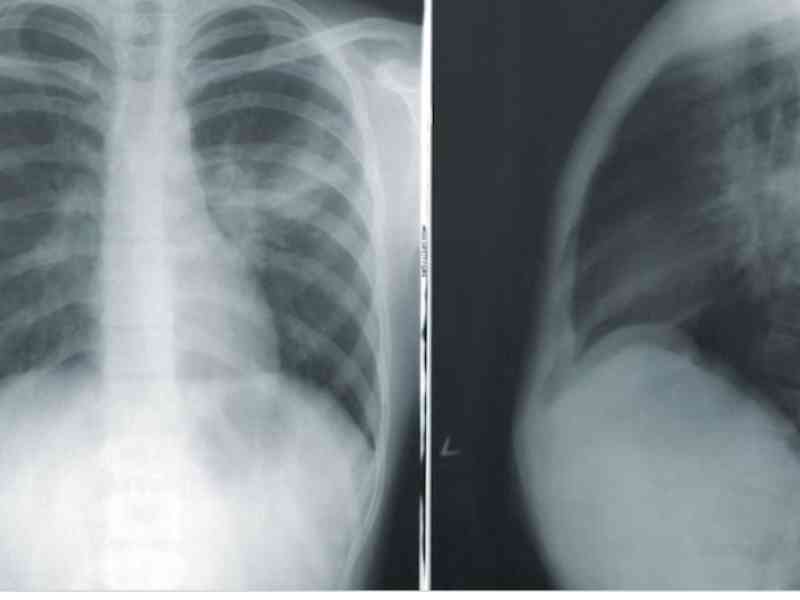

13. Walking Dead

I didn’t treat this patient, but I was on shift when this guy came in with chest pain. His EKG showed tombstone shapes, meaning he was in the middle of a cardiac episode. He told the emergency doctor, “I want a second opinion before going to the cath lab.” This EKG is unmistakable. The interventionalist had to come down to the emergency department to tell him he was having a heart attack.